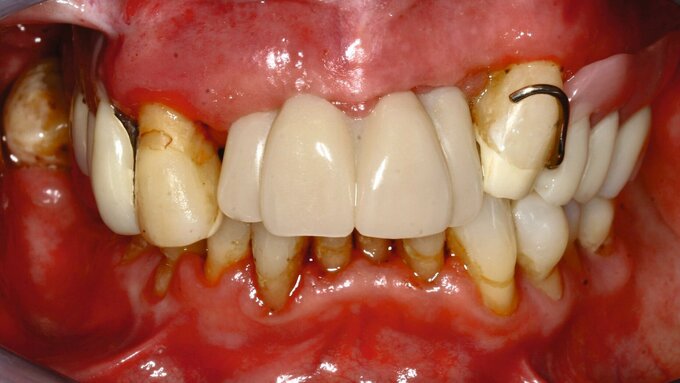

Häufig werde der chirurgische Eingriff als kritischer Schritt für die Implantattherapie gesehen. Die prothetische Phase – insbesondere die Anzahl und die Dauer der Behandlungen – sollte aber unbedingt mit bedacht werden. Beispielsweise sind Sofortimplantationskonzepte gerade bei älteren Patientinnen und Patienten sehr beliebt. Ebenso gilt es, bei der Planung auf die Ähnlichkeit des Zahnersatzes zur Restdentition beziehungsweise zur prothetischen Versorgung zu achten, da die Neuroplastizität des Gehirns mit steigendem Alter sinkt. Adaptationsschwierigkeiten sollten darum minimiert werden.